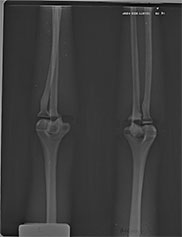

BREAK-APART PIXY Pelvis X-Ray BREAK-APART PIXY Knees X-Ray 1 BREAK-APART PIXY Knees X-Ray 2